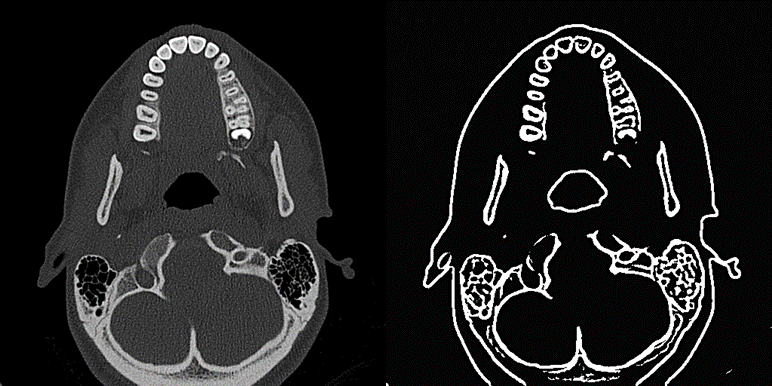

Figure 1 Original image (left) and same image after

binarization with Window size= 30 (right) and Percent contrast=100